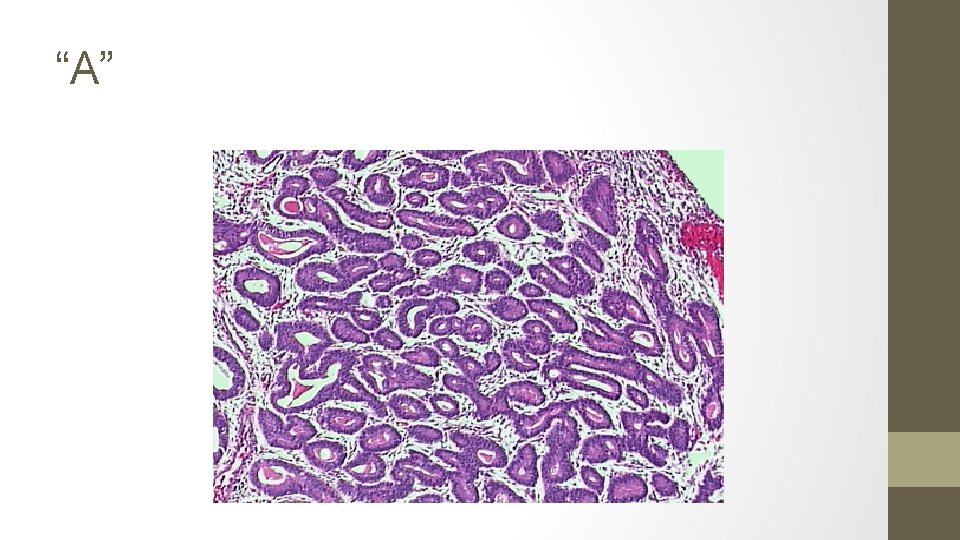

15. The biopsy samples get mixed up, the pathologist takes stress leave and you are presented with the following 5 results. Identify each smear.

A. Simple hyperplasia, no atypia (1% progression to ca) B. Complex hyperplasia, with ATYPIA (29%) C. Endometrial carcinoma (100%) D. Complex hyperplasia, no atypia (3%) E. Simple hyperplasia, with ATYPIA (8%)

Hyperplasia is the proliferation of glands, characterized by irregular size and shape, increased gland-to-stroma ratio, but with no back-to-back or HINT: Atypia is cribiform glands best diagnosed with high power Simple hyperplasia magnification o. Glandular crowding o. Mild architectural complexity o. Virutally all glands are tubular. o. Occasional glands have inspissated secretions. o. The nuclei are basal.

Complex hyperplasia o o o Extensive glandular crowding Architextural complexity The cells lining this complex gland are pseudostratified. The nuclei are elongated and hyperchromatic. Nucleoli are not prominent. The cells retain in general their orientation to the lumen. No Atypia With Atypia o o Nuclear enlargement (elongated, hyperchromatic) Nucleoli are prominent Variation in nuclear size and shape Atypical mitosis TREATMENT OF ENDOMETRIAL HYPERPLASIA NO ATYPIA Low dose Progestins MPA 10 mg qd x 6 months High dose progestins MPA 200 qd Megestrol acetate 160 qd Micronized progesterone 200 qd Mirena WITH ATYPIA Hysterectomy & BSO High dose progestins Mirena EMB q 3 -6 MONTHS

Endometrial carcinoma o. Crowded glands, with little or no stroma o. Stromal inflammatory reaction surrounding endometrial gland o. Malignant nuclei (by HPF): round, course, chromatin clumping